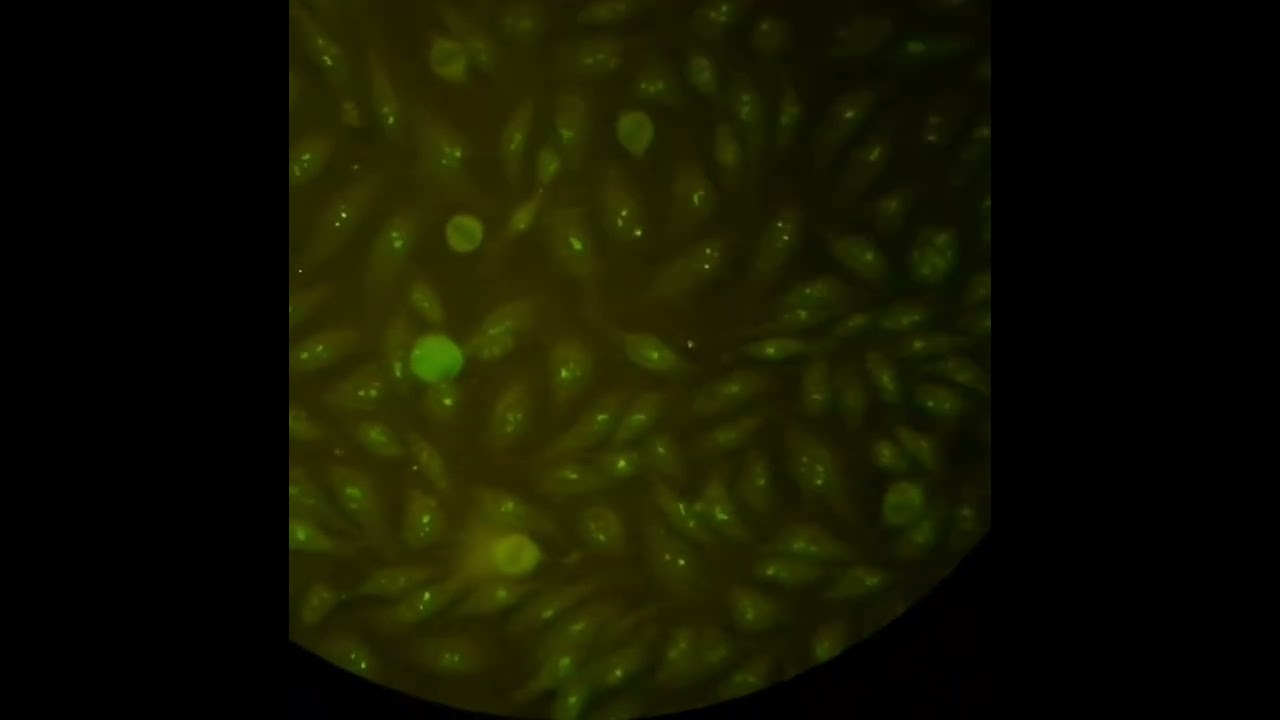

immunofluorescence test: Antibodies against U3-nRNP/fibrillarin for detection systemic sclerosis.

On HEp-2 cells interphase cells show a speckled fl uorescence of the nucleoli.

Mitotic cells show a coronary perichromosomal fl uorescence.